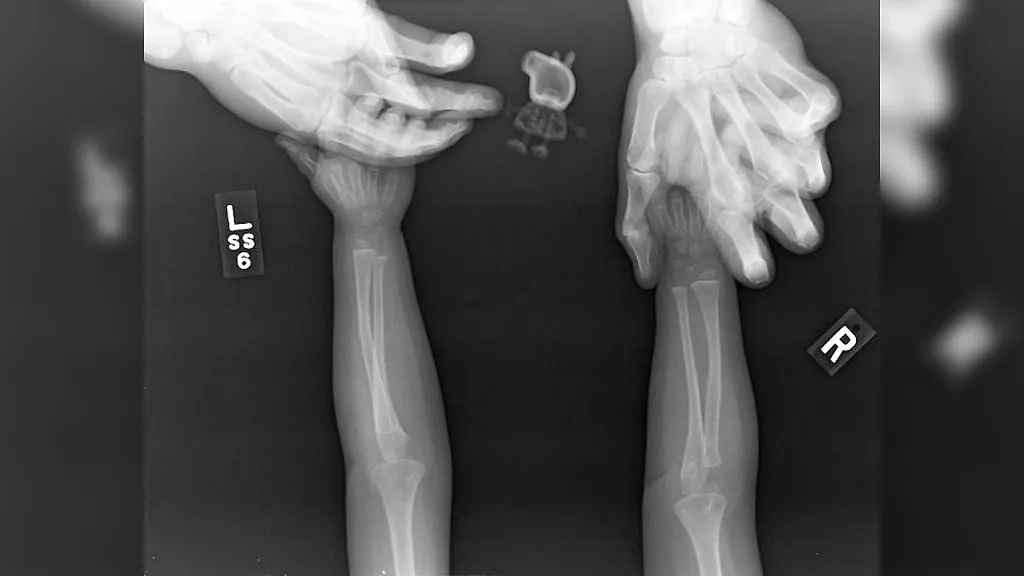

"Рентгенограмма стоп моего сына", — jsams18.

Фото © Reddit / jsams18